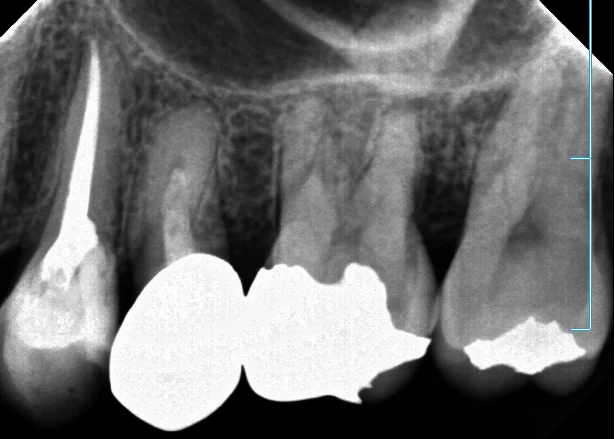

では、これが術前のレントゲンです。

初診時はプラークが詰まっていて、見えづらかったですが、拡大視野下で観察すると少し怪しかったのでレントゲンを撮ってみました。

保険のメタルインレーが入っており、その脇から中に大きく虫歯が入り込んでいます。 (画像の赤丸の所)

ただ、この歯、どうやら神経の治療をされていたようなんですが・・・ なんかこう・・・ちょろっとしか薬が入っていません。 (画像の黄色の矢印の所)

幸い根の先に膿が溜まったりはしていませんが、虫歯の期間が長かったせいか根管(神経の入っている管)の中に高度に石灰化が起こってしまっています。 (画像のオレンジの矢印の所)

要は動脈硬化みたいな感じで根管が塞がってきているイメージですね。

そのせいで根の先まで到達するのが非常に困難な状態となっています。

というのも、この塞がった根管というのがどのくらい細いかというと、髪の毛一本よりも細いんです。 本来の根管は髪の毛数本分くらいの太さはあります。 (いや、それでも十分細いんですけどね・・・!)